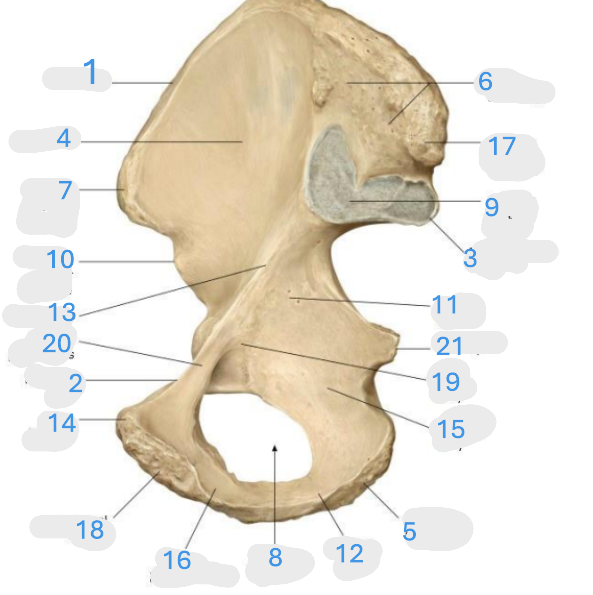

Where is the iliac crest

1

Where is the pectineal line

2

Where is the posterior iliac spine

3

Where is the iliac fossa

4

Where is the ischial tuberosity

5

Where is the iliac tuberosity

6

Where is the anterior superior iliac spine

7

Where is the obturator foramen

8

Where is the auricular surface of the ilium

9

Where is the anterior inferior iliac spine

10

Where is the ilium body

11

Where is the ischial ramus

12

Where is the arcuate line

13

Where is the pubic tubercle

14

Where is the ischium body

15

Where is the inferior pubic ramus

16

Posterior superior iliac spine

17

Where is the symphyseal surface

18

Where is the pubis body

19

Where is the superior pubic ramus

20

Where is the ischium body

21